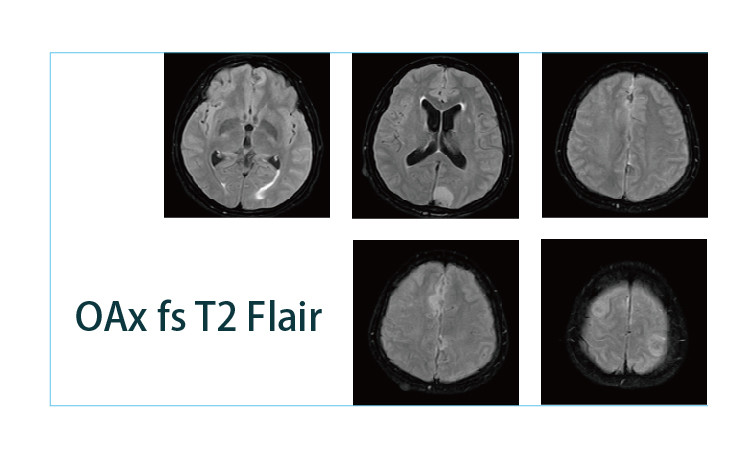

【朗润影像档案】磁共振影像病例分享(编号20190412)